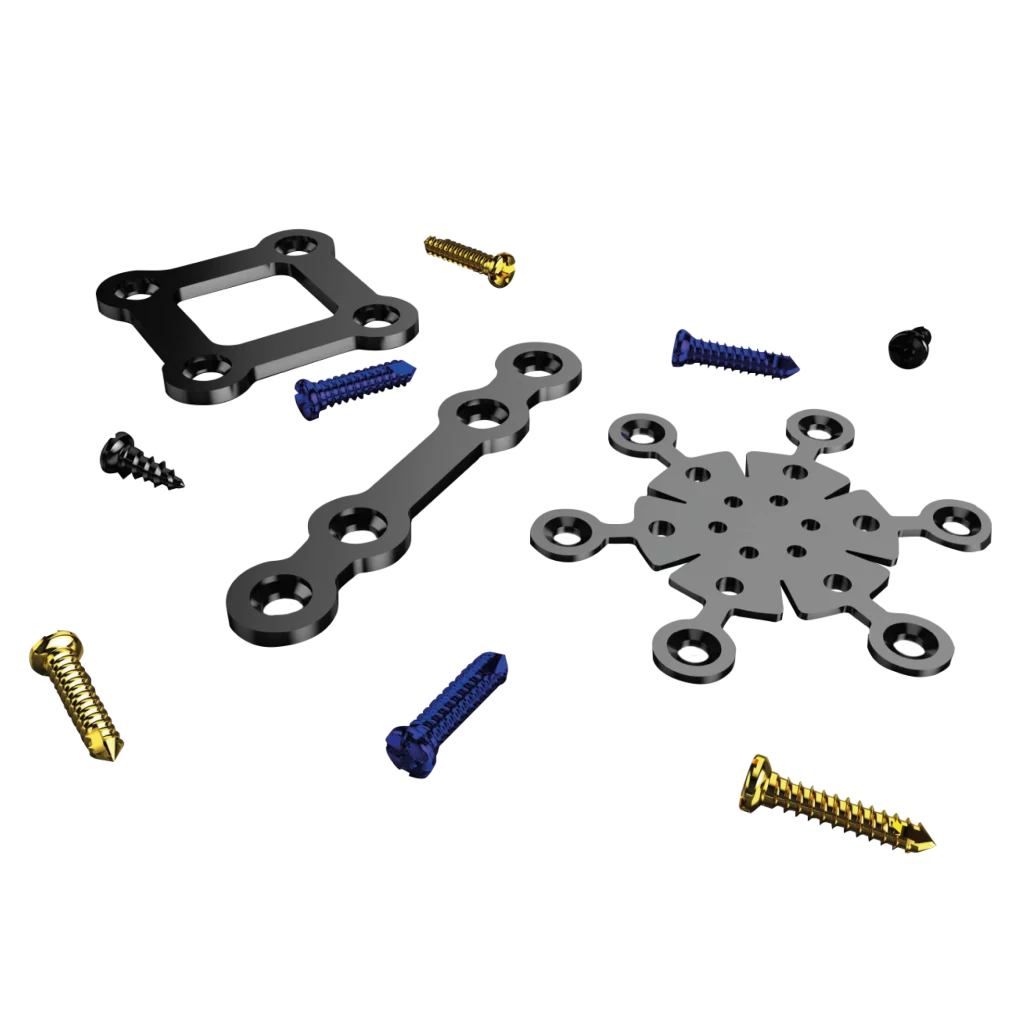

Cirurgia Ortognática

Uma gama completa de produtos dedicados à cirurgia ortognática, incluindo placas, parafusos, splints e guias cirúrgicos, impressos em 3D, para atender suas necessidades até mesmo nos casos mais complexos.